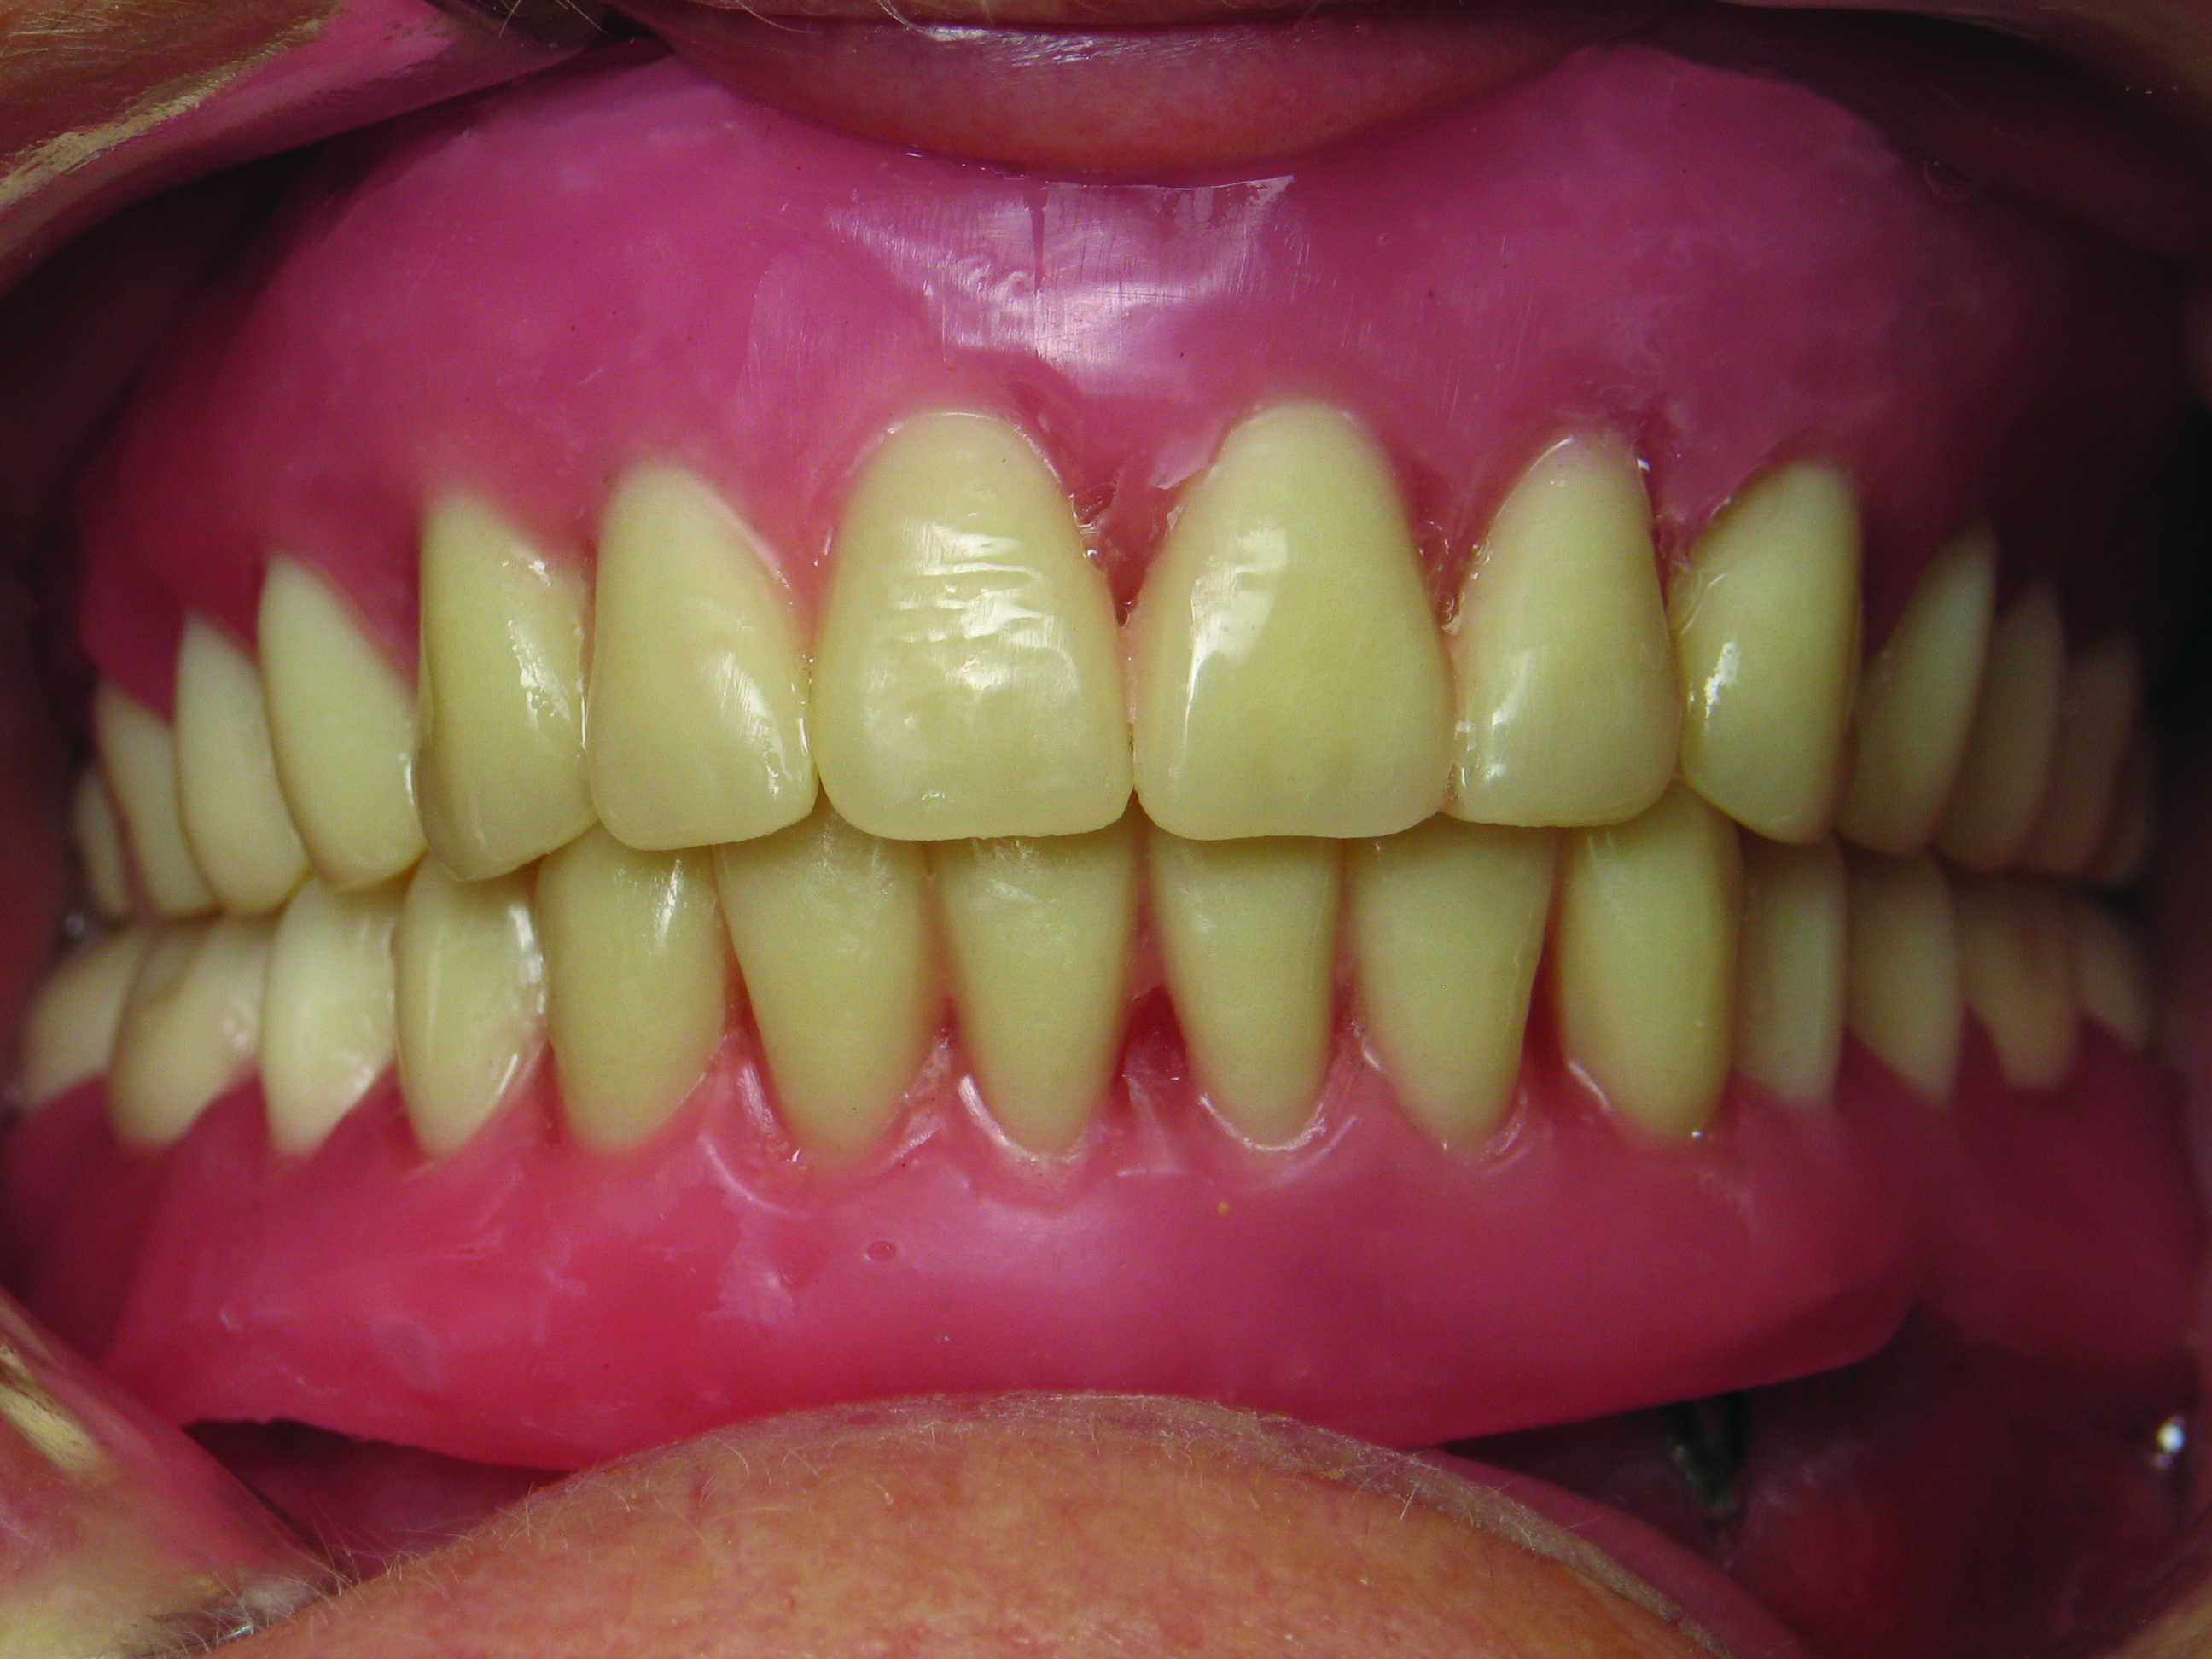

Today’s milled and printed dentures have clear advantages over their handmade counterparts. Key benefits of digital dentures include, “significantly reduced dentist time, and improved retention and digital archiving.”10 Fewer patient visits result in less chairtime, and improved retention can be attributed to the manufacturing process. As shown by other CAD/CAM manufacturing processes, virtually designed and milled or printed dentures have a better fit by reducing the human error associated with the traditional process (Figure 12 through Figure 14). Finally, digital archiving is highly beneficial for both the patient and dentist. No longer does one need to keep stone models, and if a patient relocates to another city or state, their records can be easily transferred.

Fig 13. Detail of the digital denture base.

Figure 13

Fig 14. Complete polished denture.

Figure 14